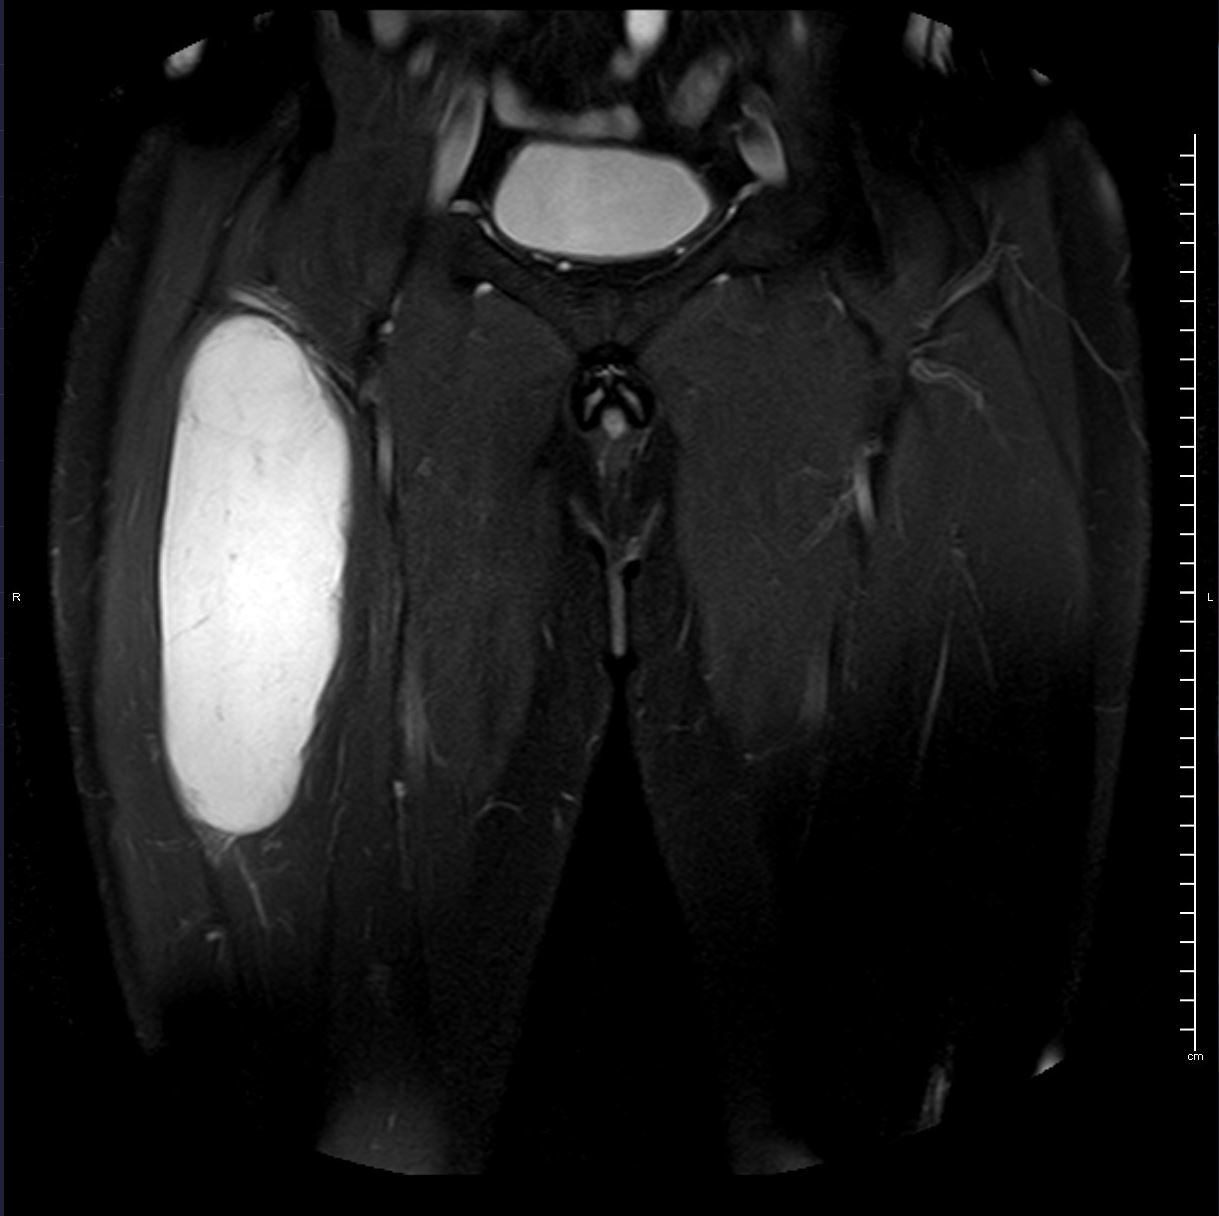

RM t2 axial

HALLAZGOS RADIOLÓGICOS